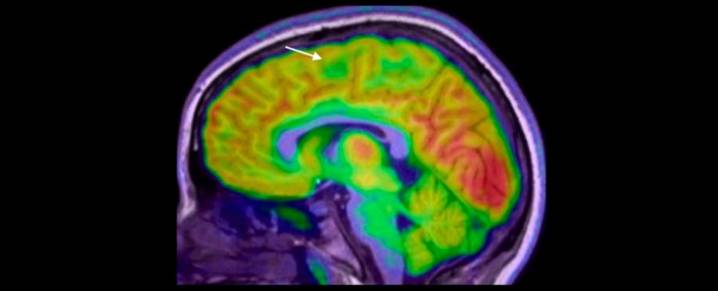

These are often missed on MRI scans – especially the smallest lesions, sometimes hidden at the bottom of a brain fold.

A team led by Emma Macdonald-Laurs, a paediatric neurologist at the Royal Children's Hospital in Melbourne, trained an AI tool on child brain images to find lesions the size of a bluebe